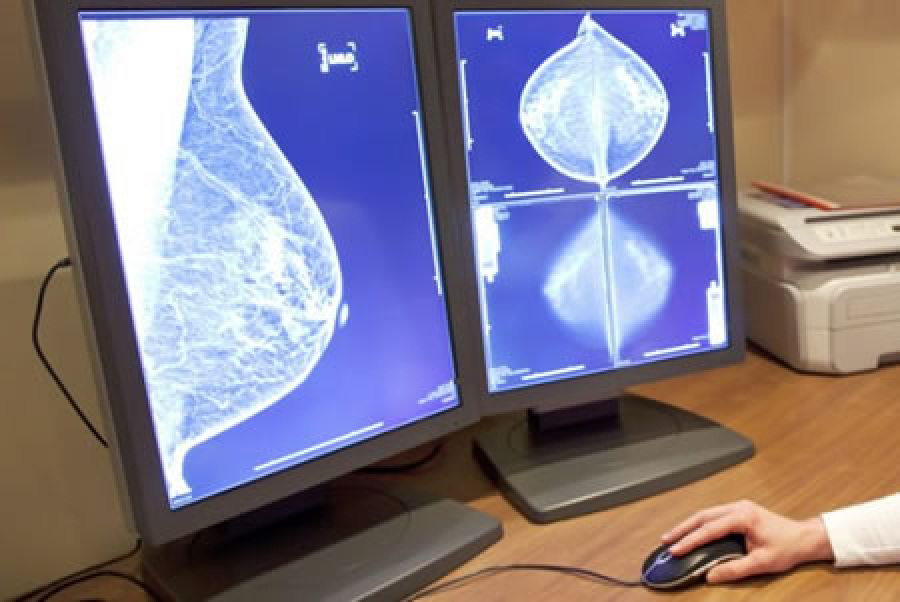

Estos fármacos anti-HER2 se indican exclusivamente para el cáncer de mama HER2 positivo, que representa alrededor del 15-20% de todos los casos de cáncer de mama. Es de suma importancia determinar el subtipo de cáncer de mama en las pacientes afectadas para poder establecer un tratamiento personalizado e innovador que sea más efectivo contra su tipo específico de cáncer.